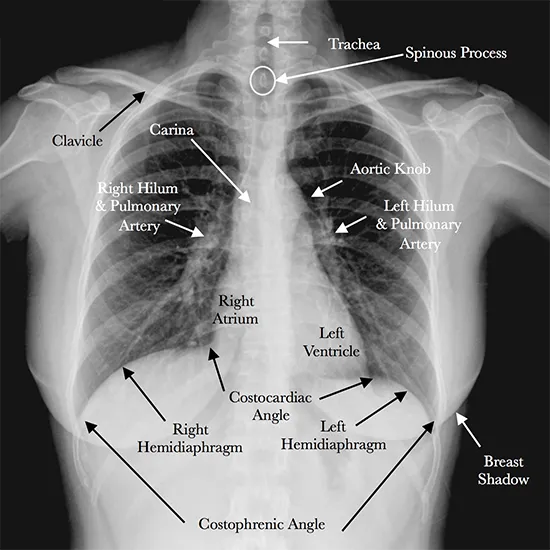

Black-and-white images will be formed by the x-ray.

The structures are studied by the radiologist as per the density of the image and underlying pathologies like: pneumonia, Tuberculosis (tb), heart failure, cancer, fluid around the heart.